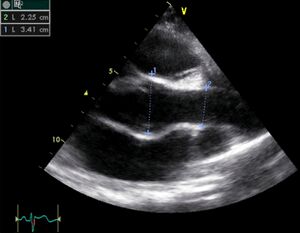

| Case description: Severe Hypertrophic Cardiomyopathy (HCM) | |

| Courtesy of: F. Windhausen, AMC, The Netherlands | |

| A2CH view | A4CH view |